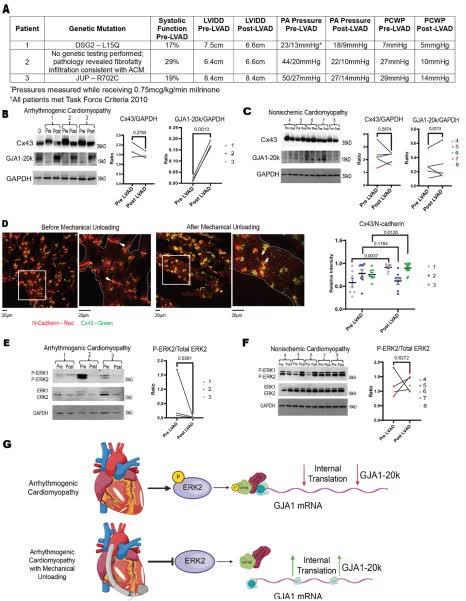

LVAD unloading augments GJA1-20k expression in patients with arrhythmogenic cardiomyopathy, but not in patients with NICM. UofU Nora Eccles Harrison CVRTI @palatinuslab #AHAJournals ahajrnls.org/4lDqh5r